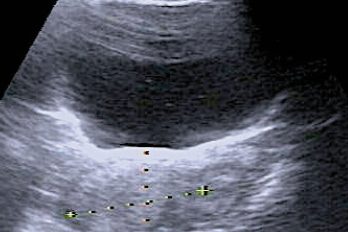

L’échographie endo-vaginale est l’examen de choix pour reconnaître le caractère bénin ou malin d’une tumeur ovarienne : 10 règles simples facilitent l’interprétation des images échographiques. ■ Introduction : le cancer de l’ovaire En Allemagne, une femme sur 72 développe un cancer de l’ovaire (1). L’âge moyen au moment du diagnostic est de 69 ans, mais la fréquence augmente…